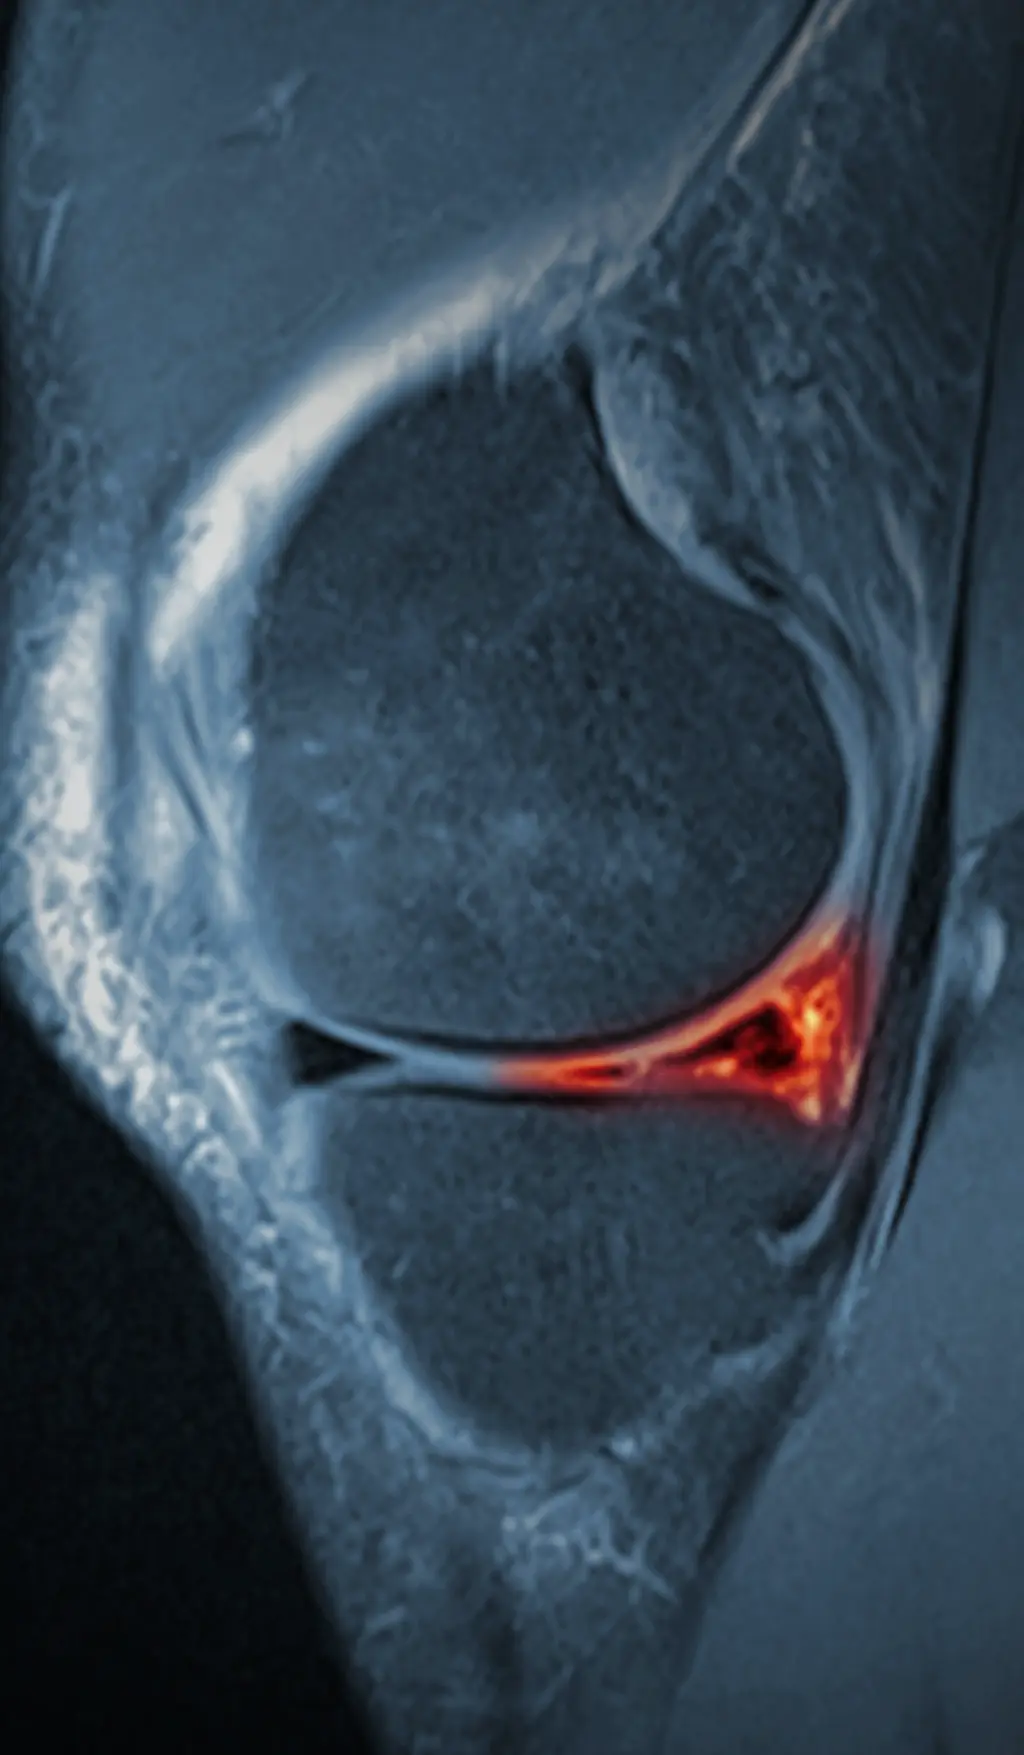

Grad 2: linearförmige Signalanhebung ohne Durchbrechung der Oberfläche Ärzte empfehlen eine konservative Therapie - also einen Meniskusriss ohne Operation zu behandeln

Source: methodisypl.pages.dev Meniskusriss KLINIK am RING Köln , Meniskusriss Grad 3: Ein kompletter Riss, der den Meniskus durchdringt, oft mit deutlichen Symptomen wie Schmerzen und Schwellungen Man kann zwischen verschiedenen Formen und Graden eines Meniskusschadens unterscheiden

Fall 2.A.KMR.15.19 Hinterhornriss des medialen Meniskus Wirbelsäulen und Gelenke Zentrum . Man kann zwischen verschiedenen Formen und Graden eines Meniskusschadens unterscheiden Wie kann man einen Meniskusriss ohne OP behandeln? Nach erfolgter Diagnostik steht die Entscheidung über die Therapie des Meniskusrisses an, hierbei sollten sich Betroffene in jedem Fall ärztlich beraten lassen.